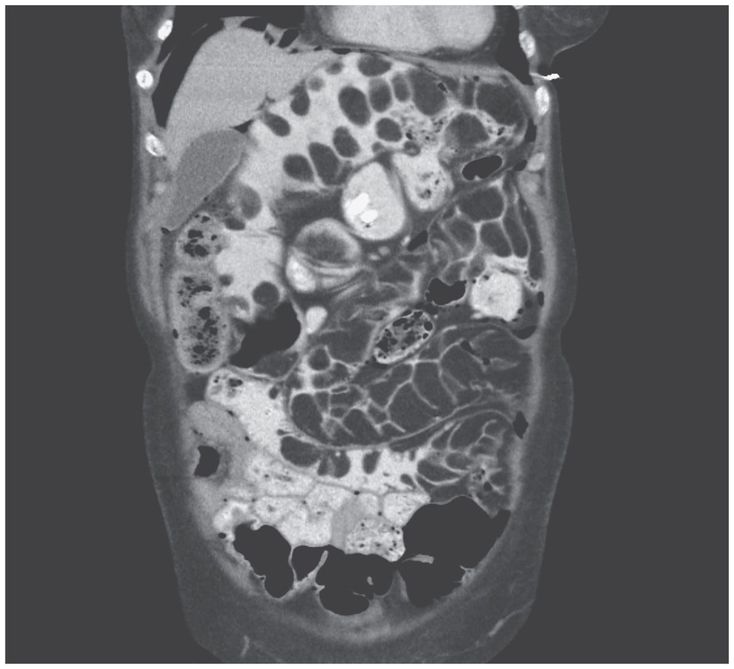

A 74-year-old woman presented to the gastroenterology clinic with a long history of bloating and abdominal distention. On physical examination, the abdomen was found to be distended but was nontender on palpation, with normal bowel sounds. Findings on computed tomography of the abdomen and pelvis were consistent with fat-containing lesions throughout the small bowel. Esophagogastroduodenoscopy showed numerous submucosal masses in the duodenum with a pillow sign (i.e., indentation of a subepithelial lesion when prodded with biopsy forceps). Unroofing of the subepithelial lesion on biopsy revealed yellow adipose tissue. Histopathological examination confirmed the presence of mature adipose tissue consistent with lipoma. Intestinal lipomatosis involves multiple lipomas in the small or large intestine. Patients may be asymptomatic or have mild symptoms or present with complications of bowel obstruction or intussusception. No specific treatment is available except for surgical management in severe or complicated cases. Surgery was not offered in this case because of involvement of the entire small bowel. At the 3-month follow-up, the patient reported a moderate reduction in symptoms after some dietary alterations.